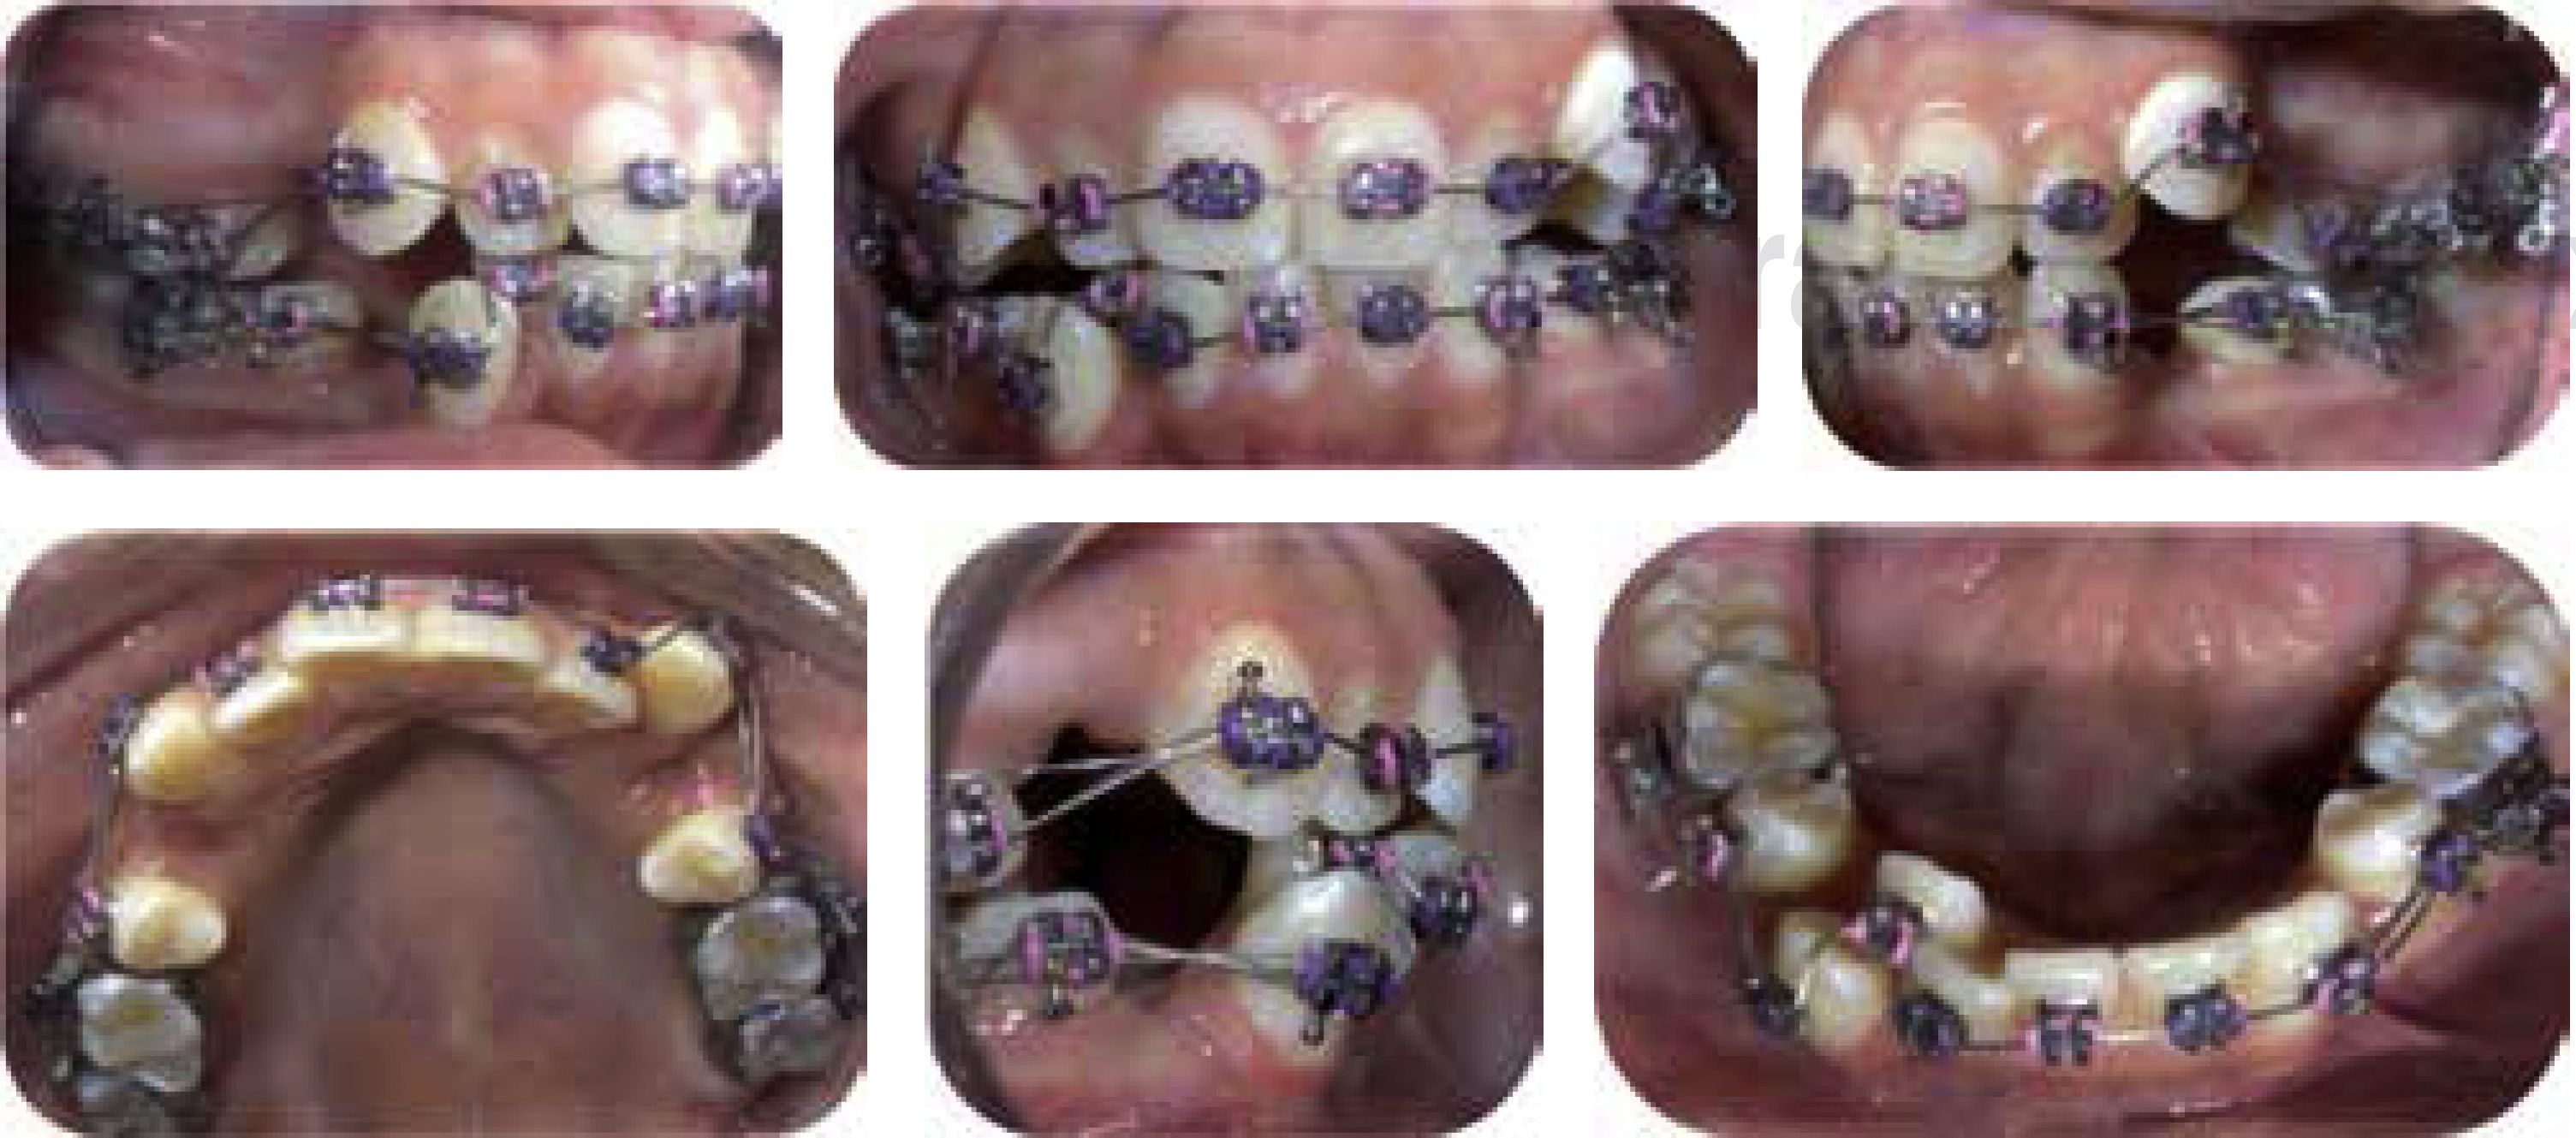

Se realizaron extracciones de primeros premolares superiores e inferiores. Colocación de bandas. Bonding de brackets superiores e inferiores prescripción Roth slot 0.022”. Fase I: nivelación y alineación inicial con arcos ligeros 0.014” NiTi. Fase II: coordinación, a base de movimientos de segundo y tercer orden ligeros, refuerzo de anclaje con microimplantes, retracción de segmento anterior con DKL y cierre de espacios, consolidación, estabilización y retención (Figuras 6 a 9).

Las fotografías extra e intraorales, las radiografías y el análisis funcional demuestran resultados completamente satisfactorios, ya que se corrigió el eje axial de los dientes y se disminuyó la biprotrusión dentoalveolar. El perfil mejoró disminuyendo la biproquelia. Se mejoró la función craneomandibular eliminándose el dolor muscular generalizado. Se logró obtener un patrón de apertura y cierre sin desviación obteniendo una apertura máxima de 38mm. Se eliminaron los hábitos bucales y se recuperó la función masticatoria correcta. Se obtuvo clase I molar y canina bilateral. Se eliminó el apiñamiento, se corrigió la sobremordida vertical y horizontal, se corrigieron las líneas medias y se mejoró la forma de las arcadas (Figuras 10 a 12).